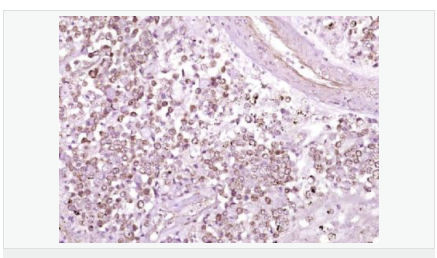

交叉反應:Human,Mouse,Rat(predicted:Dog,Pig,Cow,Rabbit) 推薦應用:WB,IHC-P,IHC-F,IF,ELISA

| 產(chǎn)品應用 | WB=1:500-2000 ELISA=1:5000-10000 IHC-P=1:100-500 IHC-F=1:100-500 IF=1:50-200 (石蠟切片需做抗原修復) not yet tested in other applications. optimal dilutions/concentrations should be determined by the end user. |